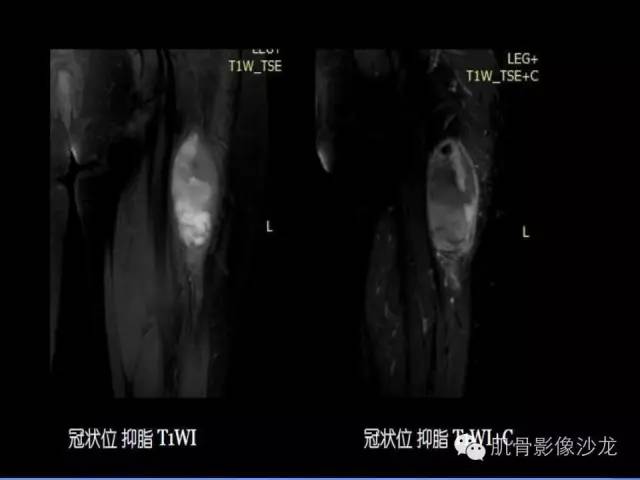

【病例】恶性外周神经鞘膜瘤1例MR影像表现